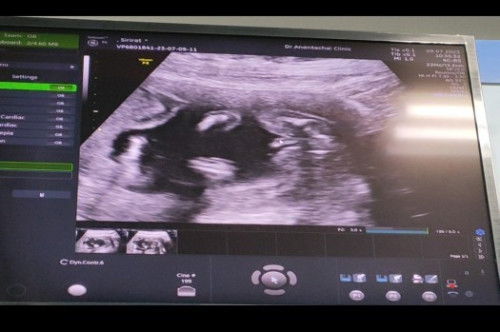

จับคำๆหน้าท้องดู เคยรู้สึกว่าได้ยินเสียงหัวใจลูก แต่มี2-3วันนี้ ที่ไม่ได้รู้สึกหรือรู้สึกเบาลง

ตอนนี้ประมาน10สัปดาห์ค่ะ ได้ซาวน์ไป1ครั้ง มีนัดวันที่9/5/66 จิตตกมากเลยค่ะ ไม่สามารถว่าไปหาหมอก่อนดีมั้ยค่ะ กลัวน้องหัวใจหยุดเต้น แต่อาการอื่นๆไม่มีอะไรเลยค่ะ ไม่แพ้ท้อง ไม่หิวหรืออยากกินอะไร ไม่มีเลือดออก ไม่มีตกขาว หรือเราจิตตกไปเองค่ะ #ท้องแรกคะ #ขอคำแนะนำหน่อยค่ะ #คุณแม่ๆช่วยแนะนำหน่อยค่ะ